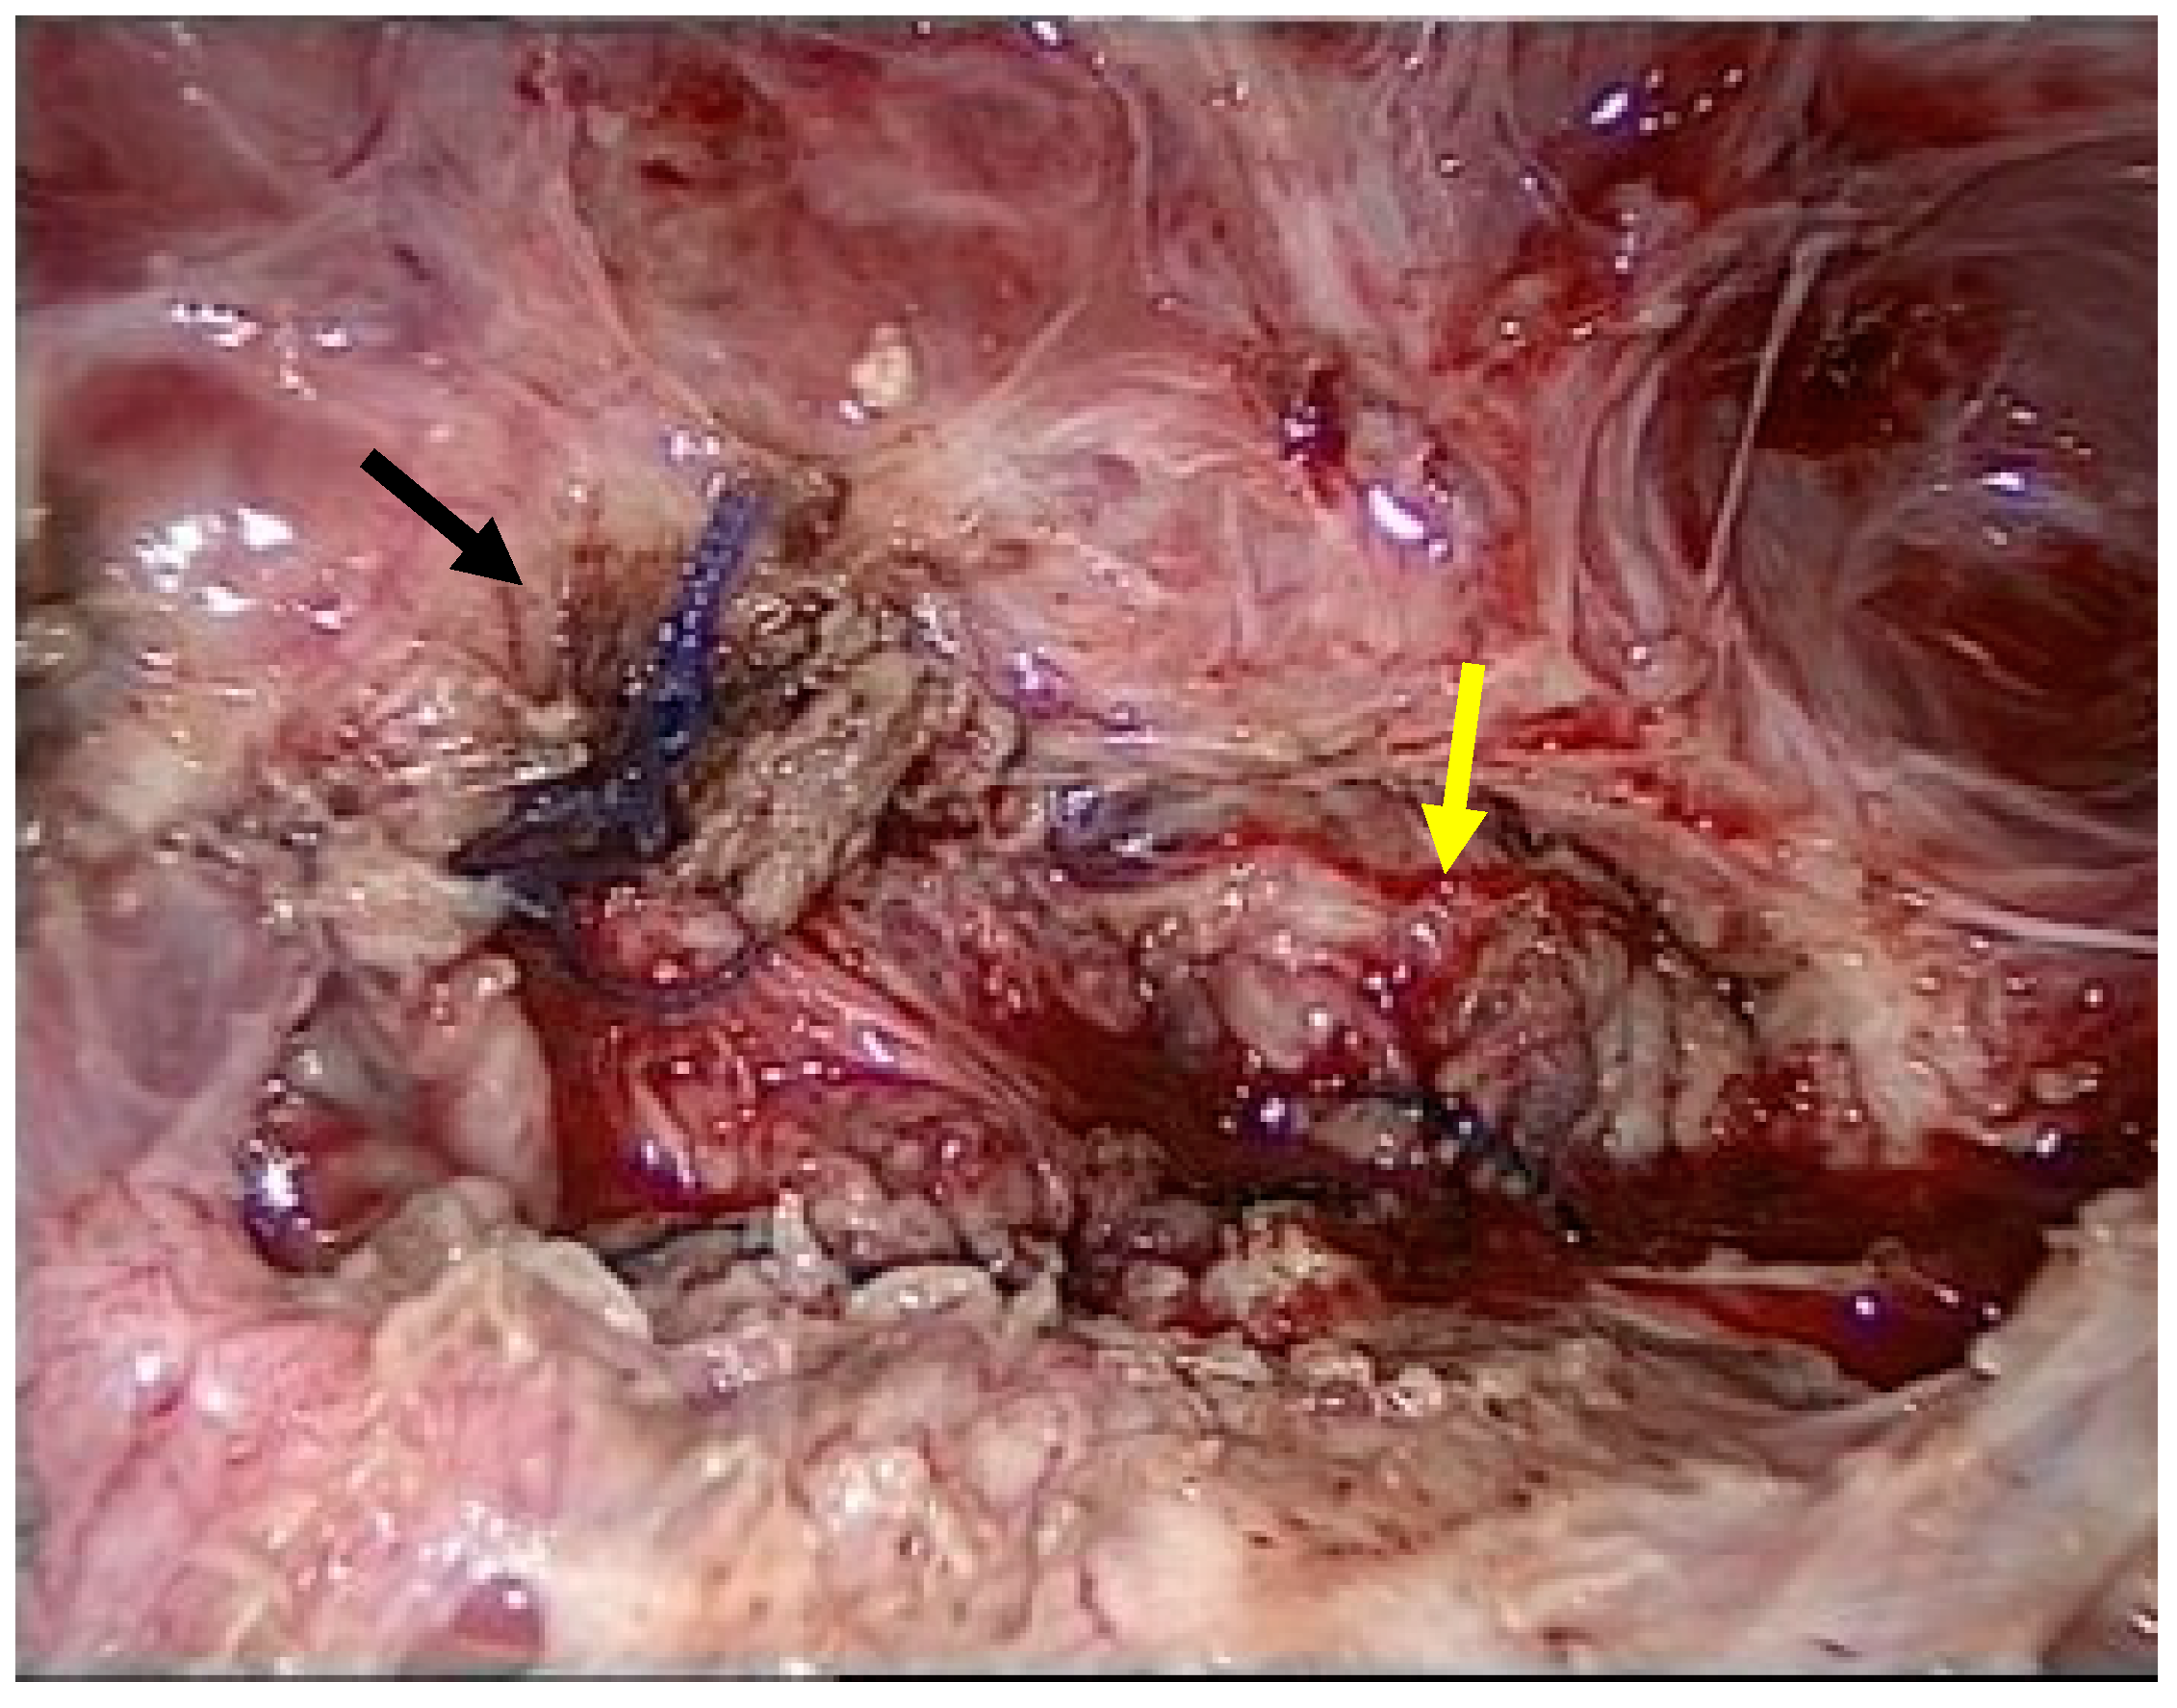

A 32-year-old postnatal mother was referred to our tertiary university center complaining of urine leakage via the cervix uteri after vacuum-assisted delivery with impending fetal asphyxia five days prior to referral. In the past, the patient had delivered a child by cesarean section and another child by vacuum-assisted delivery. Laboratory tests did not reveal any signs of anemia or infection. First, methylene blue was injected into the bladder through a urinary catheter. Blue urine was observed when the speculum was inserted into the vagina, indicating the presence of vesicouterine fistula. In addition, abnormal communication was suspected, as transvaginal ultrasound showed a bladder wall in close contact with the anterior surface of the uterus with no demarcation line (Figure 1).

Figure 1.

Transvaginal ultrasound using power Doppler demonstrating communication (yellow arrow) between the uterine cervix (green arrow) and bladder (red arrow).